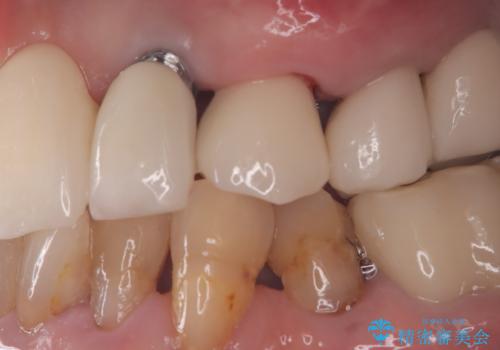

![[ インプラント体・カスタムアバットメント・ジルコニアクラウン ] インプラントの構造の症例 治療前](https://seimitsushinbi.jp/wp/wp-content/uploads/2024/02/d7b3d7509c0cc77833268d7096e1730b-500x350.jpg?v=1708928260)

![[ インプラント体・カスタムアバットメント・ジルコニアクラウン ] インプラントの構造の症例 治療後](https://seimitsushinbi.jp/wp/wp-content/uploads/2024/02/4f5d249988cfa0d7689dd16755d46820-500x350.jpg?v=1708928265)